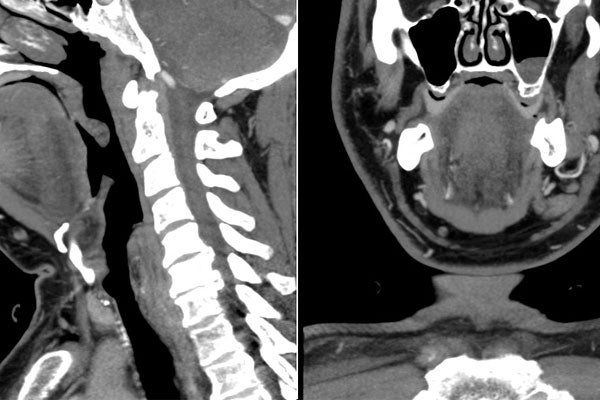

diagnostic images courtesy the Faculty of Medicine

This year, the Ontario Forensic Pathology Unit and the Faculty of Medicine’s departments of medical imaging and laboratory medicine and pathobiology worked together to help residents gain forensic radiology experience. And, as the diagnostic radiology residents rotated through the provincial forensic pathology unit, they worked with forensic pathologists to analyze medical images (CT and MRI) to help determine better approaches for autopsies.

Ontario's Provincial Forensic Pathology Unit conducts post-mortem examinations on people who have died suddenly and unexpectedly. Since moving to a new facility in 2013, the unit has integrated advanced tools such as full-body CT scans and MRIs into their practice. Forensic pathologists use these studies to plan their postmortem examinations and to provide evidence during criminal proceedings.